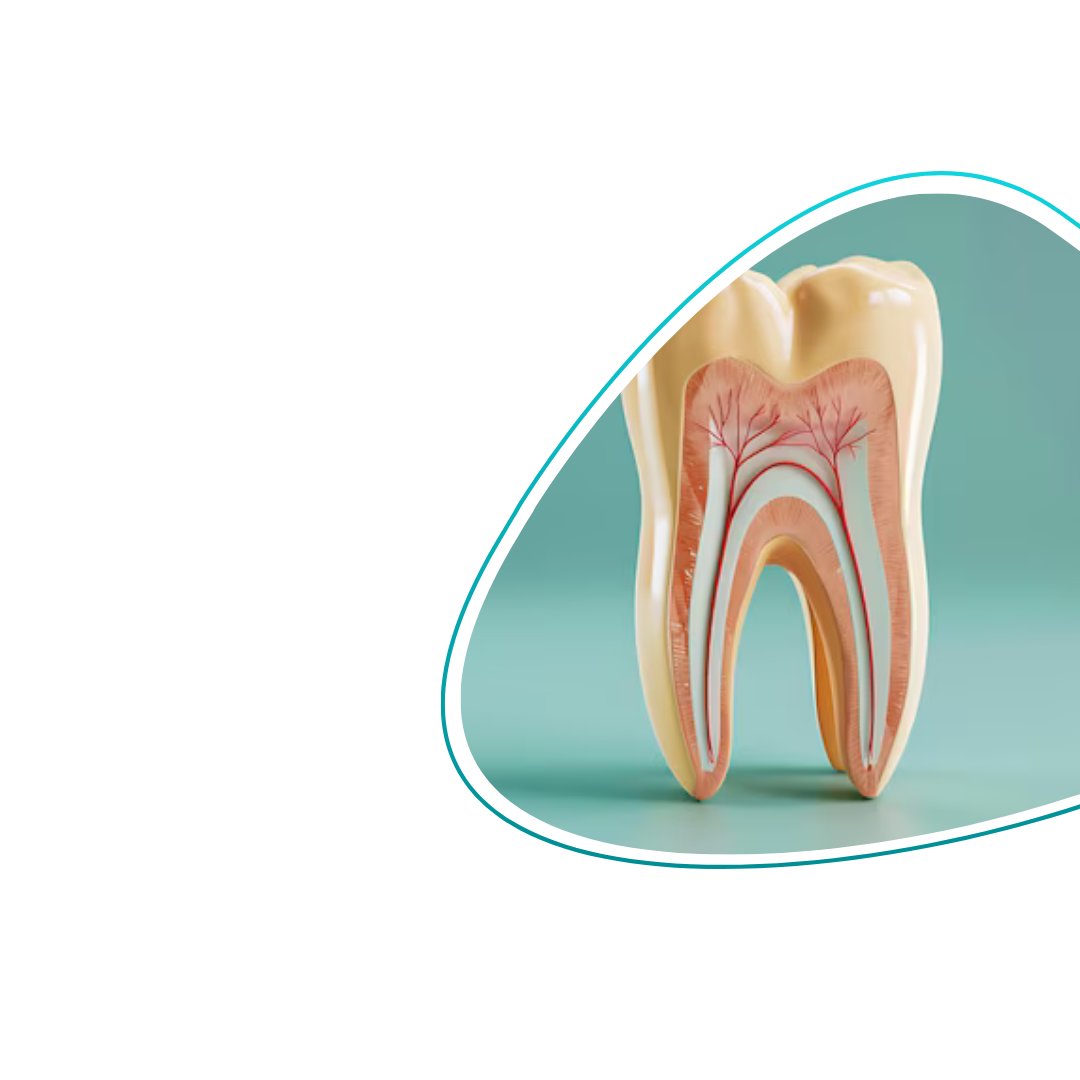

Што претставува ЕНДОДОНЦИЈА?

Ендодонцијата претставува третман со кој се спасува забот кога е оштетен или инфициран внатрешно. Со современи техники и безболна процедура, се отстранува инфекцијата и се зачувува природниот заб. Благодарение на овој третман, забот повторно станува целосно здрав и безболен.

Кога воспалението го зафаќа нервот на забот, се врши третман на коренски канали со цел да се отстрани инфекцијата и да се зачува природниот заб. Постапката е безболна и целосно безбедна.